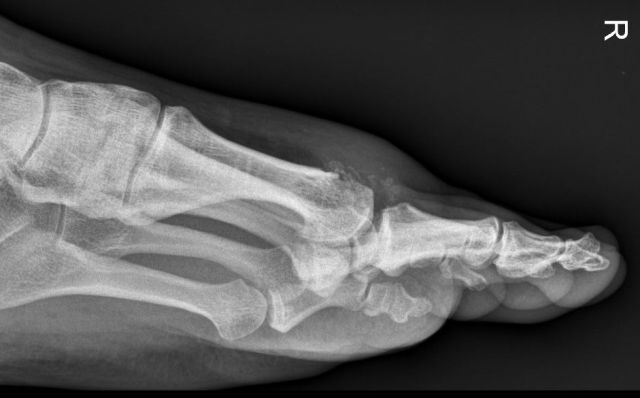

Als Therapieoption, bevor eine Versteifungsoperation (Arthrodese) überlegt wird, kommt eine sogenannte Cheilektomie (Gelenkslippenabtragung) in Betracht. (Dabei werden sowohl am Grundglied als auch am Metatarsalköpfchen des Großzehenstrahls alles störenden Knochen-, Knorpel- und Kapselanteile entfernt, um einen besseren Bewegungsumfang zu erreichen und das Schmerzniveau zu senken.

Bei dieser Behandlungsoption ist eine minimalinvasive Operationsmethode unbedingt zu empfehlen, um das chirurgische Risiko und den Weichteilschaden möglichst gering zu halten. Damit können die Patienten frühzeitig mobilisiert und in die Vollbelastung geführt werden.